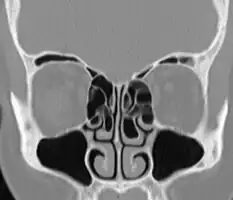

Concha bullosa

A concha bullosa is a pneumatized (air-filled) cavity within a nasal concha, also known as a turbinate.[1]

Bullosa refers to the air-filled cavity within the turbinate.[1] It is a normal anatomic variant seen in up to half the population. Occasionally, a large concha bullosa may cause it to bulge sufficiently to obstruct the opening of an adjacent sinus, possibly leading to recurrent sinusitis[1] and various head pains related to areas innervated by the trigeminal nerve.[2] In such a case the turbinate can be reduced in size by endoscopic nasal surgery (turbinectomy). The presence of a concha bullosa is often associated with deviation of the nasal septum toward the opposite side of the nasal cavity.[3]